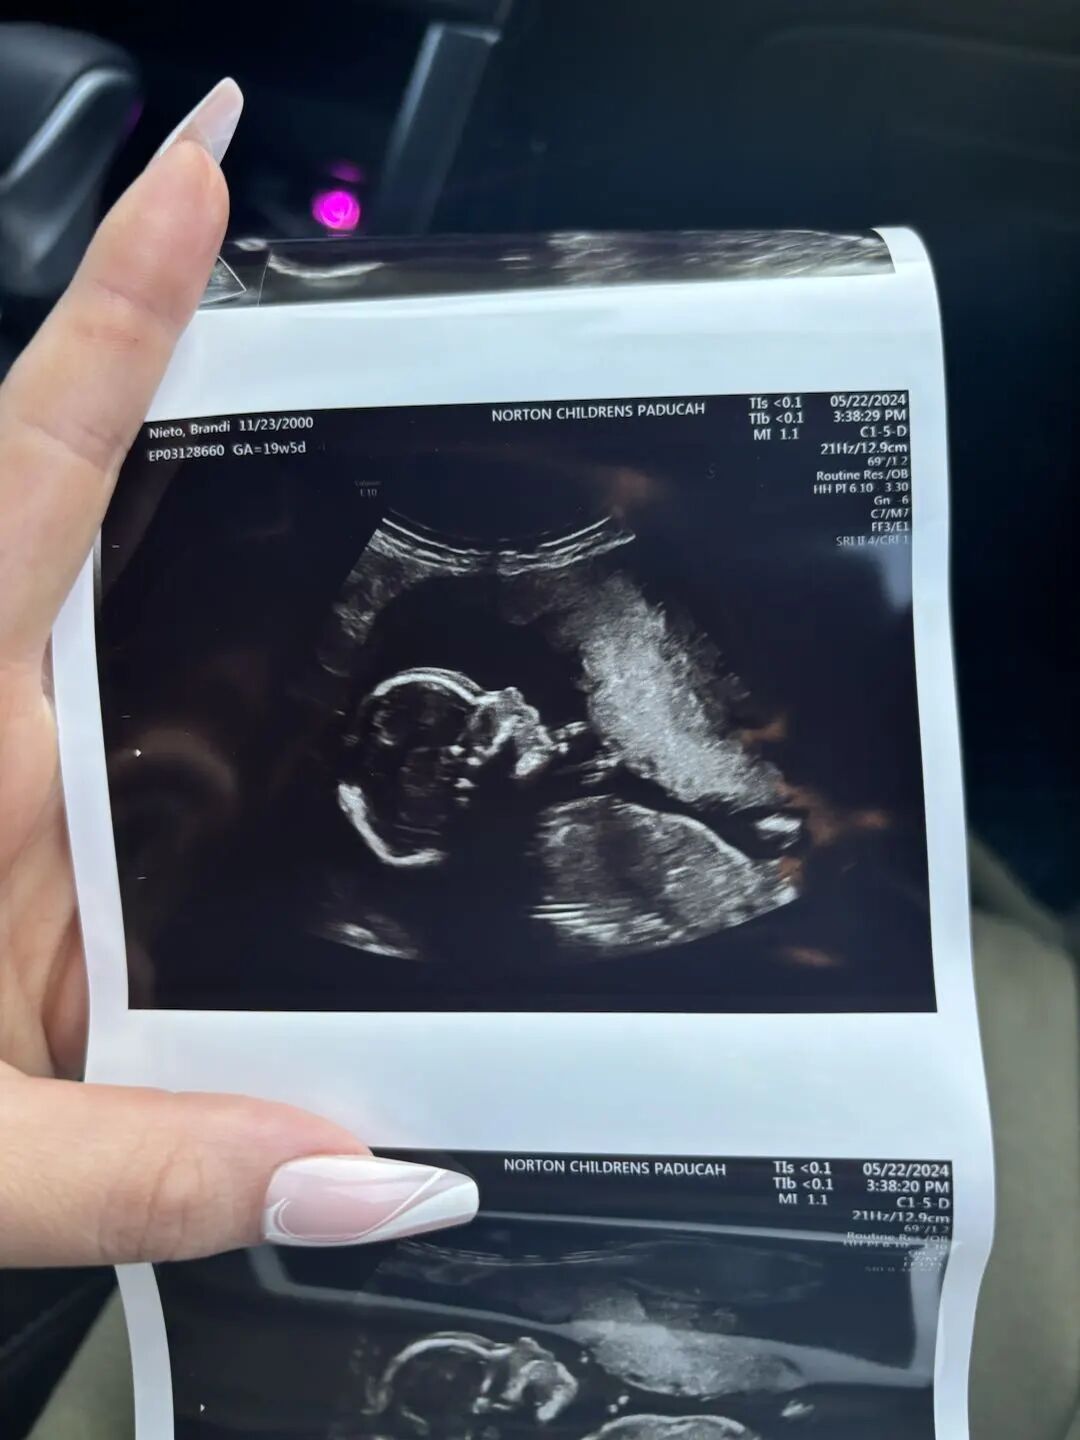

在爱妈B的悉心照料和监护下,怀孕进程一切顺利,宝宝已经健康成长到19周,期待下次的更新。